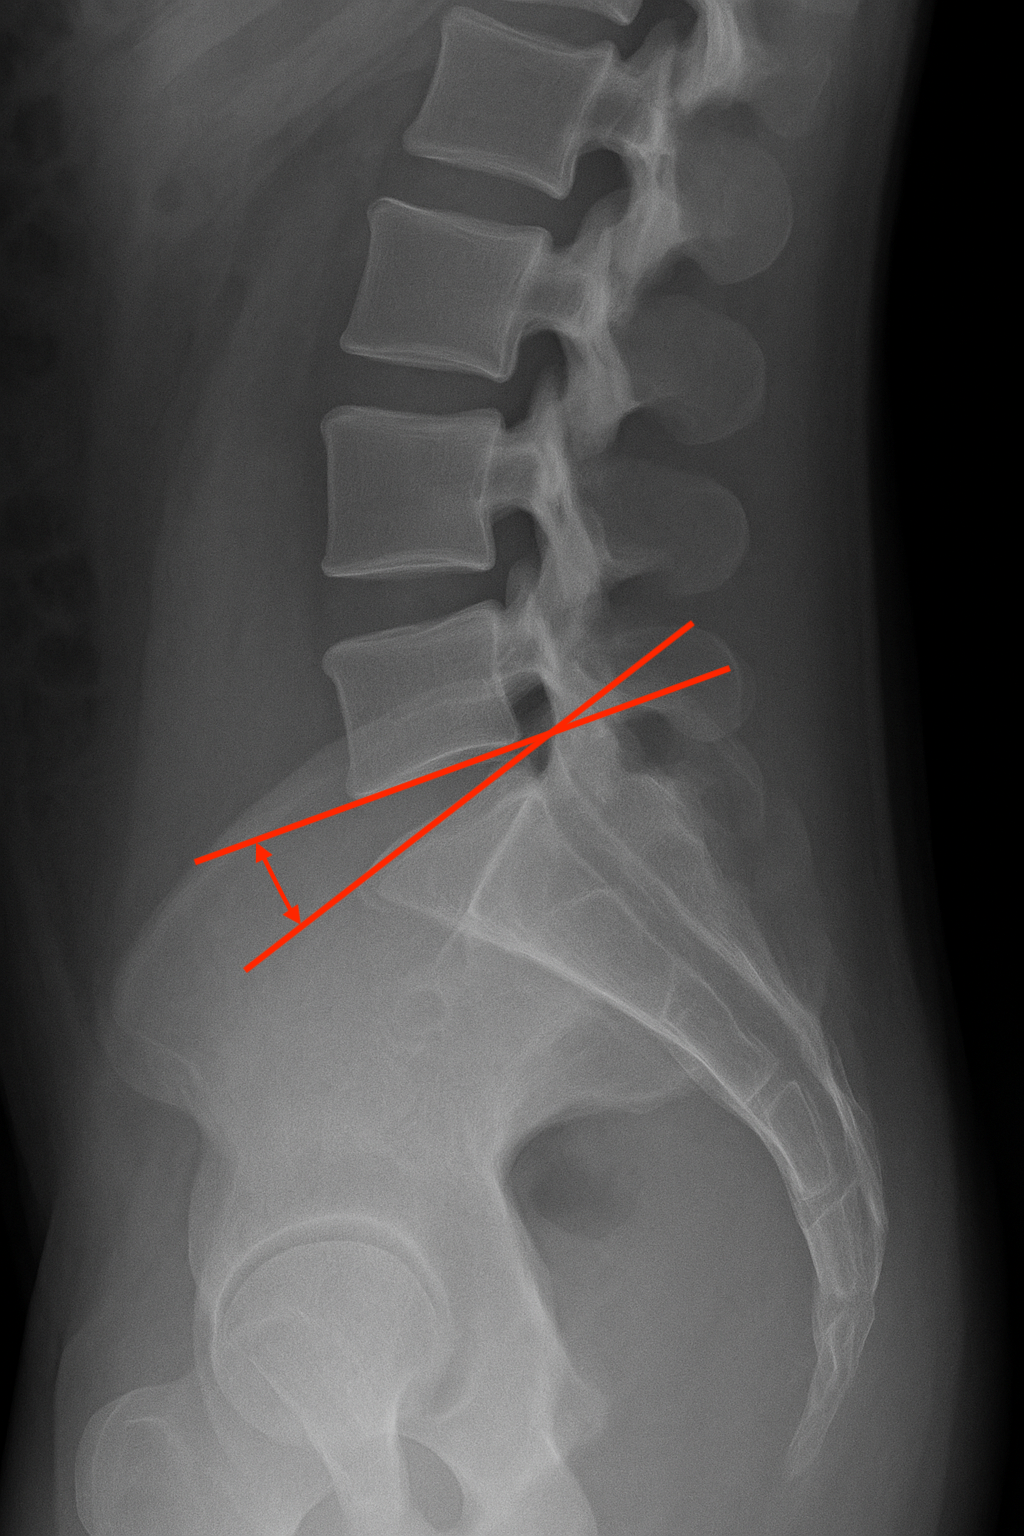

요추천골 디스크 각도는 말 그대로 요추 5번(L5)와 천추 1번(S1) 사이의 디스크 각도를 말합니다. 이 각도는 척추의 전만과 체중분산 그리고 허리의 유연성에 직접적인 영향을 줍니다.

어떻게 측정할까요?

1️⃣ 요추 5번(L5) 하부 척추체와 평행한 선을 긋는다.

2️⃣ 천추 1번(S1) 상부 척추체와 평행한 선을 긋는다.

3️⃣ 두 선이 이루는 각도를 측정하면 됩니다.

정상범위

⭐️ 정상범위 : 10도 에서 15도 ⭐️

만약. 10도 이하일 경우는 일자 허리(Flat back) 혹은 디스크 퇴성을 의심하고 있습니다. 그리고 15도 이상일 경우는 허리 전만(Lumbar lordosis)이 과하게 되어 있을 가능성이 높습니다.